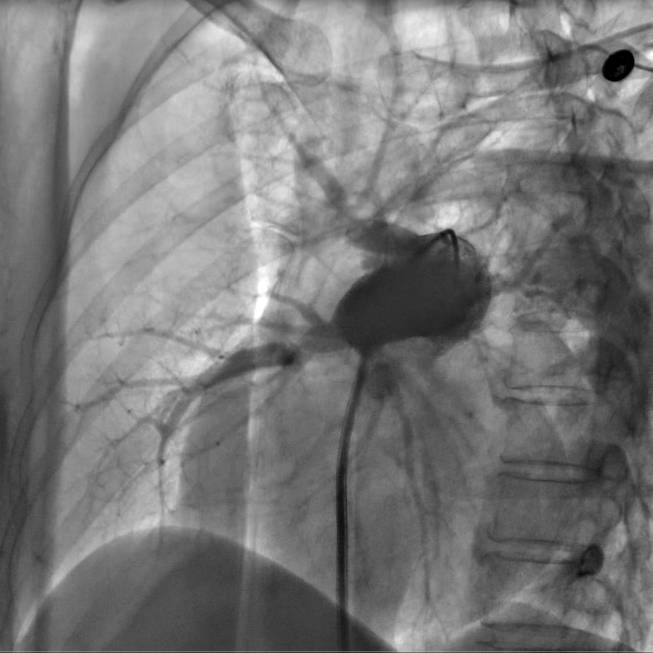

右肺动脉造影示右肺动脉多支血管重度狭窄及次全闭塞

手术由心脏中心主任马翔、副主任医师吕文魁及戴远辉完成,团队分别依次对患者右肺动脉A10段、A5段、A1段行球囊扩张,先用2.0mm的球囊以6—12atm扩张,再使用3.0mm的球囊逐级扩张,球囊扩张后患者胸闷症状即刻好转,术后8小时已下地行走,目前各方面生理指标达到预期,即将出院。